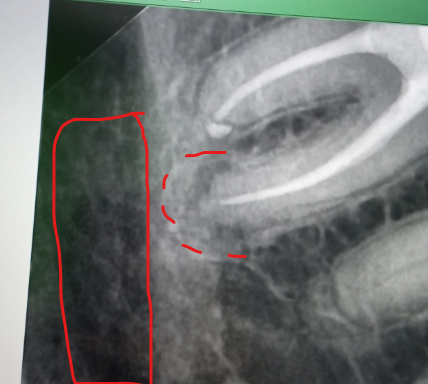

alewka213213 Опубликовано 11 декабря, 2024 Автор Поделиться Опубликовано 11 декабря, 2024 (изменено) 7 часов назад, Carioznik сказал: Не знаю, нужно разбираться и не по интернету , а произвести нормальный осмотр, собрать анамнез, посмотреть все рентгенологические исследования, возможно, сделать ещё дополнительные и тогда уже что-то, более- менее, можно будет сказать. Извиняюсь за еще один вопрос, а это что за область (отметил красным)? Если до этой области дойдет воспаление, будет худо? Просто подозреваю, что это костная ткань челюсти или нерв какой-то. А может просто снимок такой) Изменено 11 декабря, 2024 пользователем alewka213213 Ссылка на комментарий

АнтонТЛТ Опубликовано 11 декабря, 2024 Поделиться Опубликовано 11 декабря, 2024 Это нижнечелюстной канал, в нем проходят нерв и сосуды. Как правило не затрагивается даже при очень сильных воспалениях. Ссылка на комментарий

alewka213213 Опубликовано 11 декабря, 2024 Автор Поделиться Опубликовано 11 декабря, 2024 1 час назад, АнтонТЛТ сказал: Это нижнечелюстной канал, в нем проходят нерв и сосуды. Как правило не затрагивается даже при очень сильных воспалениях. А если выделенная мной область - область воспаления, то шансы высоки, что воспаление затронет нижнечелюстной канал? Выглядит так, будто очень близко воспаление Ссылка на комментарий

АнтонТЛТ Опубликовано 11 декабря, 2024 Поделиться Опубликовано 11 декабря, 2024 Не высоки, воспаление пойдет по пути наименьшего сопротивления (там где кость мягче) Ссылка на комментарий